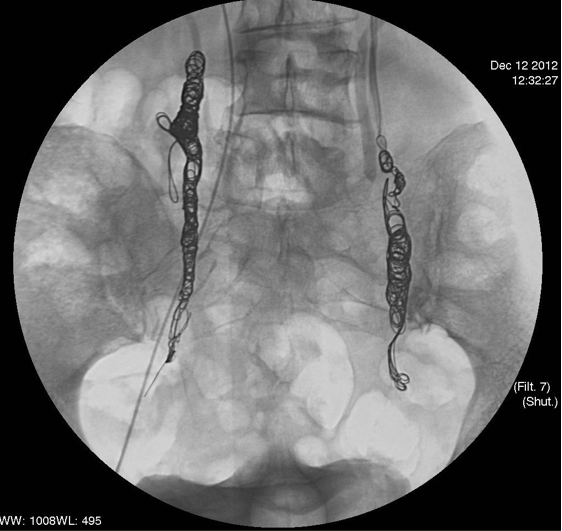

| 高质量的静脉造影一直是盆腔充血综合症诊断的金标准。高质量的静脉造影的定义,和获取方法是值得进一步探讨的问题。通常在病人平卧的情况下,影响高质量盆腔静脉造影的质量。一个可以半立位的胃肠造影床可能是获取高质量盆腔静脉造影的关键。 卵巢静脉/子宫弓形静脉>5mm;卵巢静脉自由返流;返流超过中线;股内侧和外阴静脉充盈 双侧卵巢静脉功能不全,盆腔静脉曲张

卵巢静脉造影分级 【Siqueira 2016】  I级:肾静脉造影,左侧卵巢静脉有明确返流 II级:造影剂返流至扩张的卵巢静脉和子宫周围静脉 III级:造影剂反流至扩张的卵巢静脉和子宫周围静脉,并跨过中线直至对侧盆腔级卵巢静脉 |